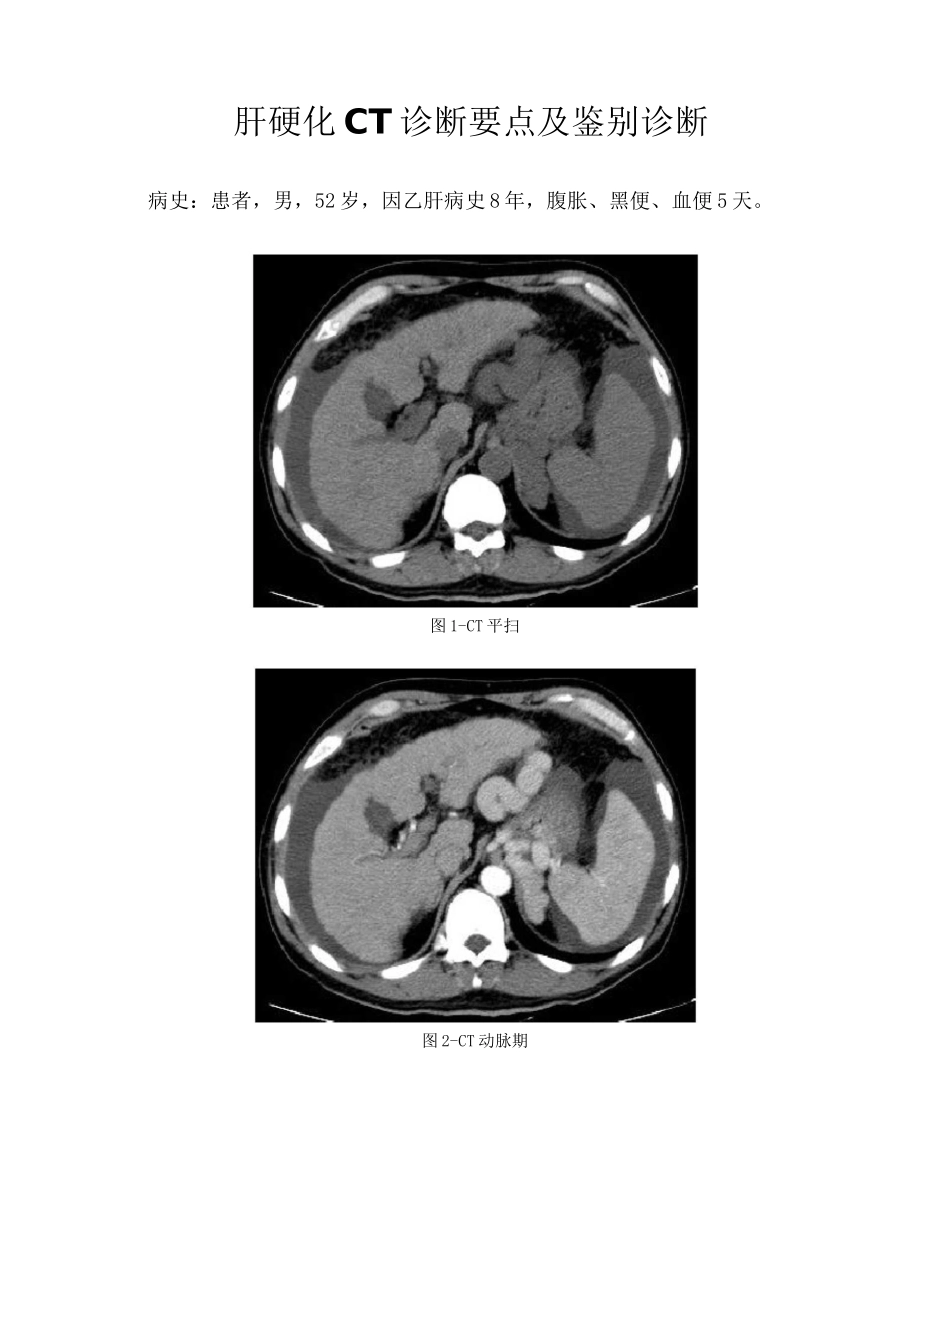

肝硬化 CT 诊断要点及鉴别诊断病史:患者,男,52 岁,因乙肝病史 8 年,腹胀、黑便、血便 5 天。图 1-CT 平扫图 2-CT 动脉期图 3-CT 门脉期4-CT 平衡期基础解剖影像:图 5图 5 为所示病例同层面正常腹部 CT 增强门脉期图片,蓝色箭头所示为正常肝脏右叶,其内见强化血管影,黄色箭头所示为正常胃,其内可见高密度对比剂影像,棕色箭头为下腔静脉,白色箭头所示为脾脏,绿色箭头所示为胰腺体尾部,其背侧贴边见强化脾静脉。本图节选自《CT 与MRI 断层解剖学袖珍图谱》。图 1图 2图 3图 4CT 平扫(图 1):蓝色箭头所示为肝脏体积缩小,边缘呈波浪样凹凸不平,白色箭头所示为脾脏体积增大,超过 5 个肋单元,肝脾周围见弧形水样密度影。CT 增强动脉期(图 2)肝脾周围积液对比明显,注意脾脏呈花斑样强化。CT 增强门脉期(图 3)黄色箭头所示为胃底静脉及食管下段静脉、腹主动脉左旁静脉明显扩张走行迂曲 oCT 增强延迟期(图 4)所示见肝脏比例欠协调,可见弥漫大小不等结节影,与肝组织强化程度相同。影像描述:肝脏体积缩小,形态不规整,边缘凹凸不平,各叶比例不协调,肝实质见弥漫结节样等密度影,大小约 0.3-1.3cm,界清,未见强化。脾脏体积增大,密度未见异常。食道下段、胃底区域及腹主动脉左旁见多发迂曲增粗静脉血管影,部分血管汇入左肾静脉。腹腔内可见游离液体影。影像诊断:肝硬化、脾大、腹水、侧支循环开放并胃肾分流分析思路:1. 临床病史:老年男性,乙肝病史 8 年,腹胀、黑便、血便 5 天,均提示肝脏病变致消化道出血可能。2. 部位及形态:肝脏体积缩小,边缘凹凸不平,肝门、肝裂增宽,提示肝硬化可能;其内见多发等密度结节,考虑为再生结节,不除外癌变可能;肝脾周围见水样密度影,提示腹腔积液;胃底区域、食管下段、腹主动脉左旁见迂曲强化血管影,提示侧枝循环开放及左肾静脉、胃底静脉分流。以上均为典型肝硬化表现。最后诊断:肝硬化。知识巩固:肝硬化1.临床表现:常见病因为病毒性肝炎、自身免疫性肝炎及酗酒。早期,肝细胞弥漫性变形、坏死;中晚期大量纤维组织增生,形成再生结节,肝脏变形、变硬,继发门静脉高压,最后可变成不典型增生结节,导致肝细胞癌。常见临床表现为食欲缺乏、腹胀、黄疸、腹水、呕血和肝性脑病。2.影像特点:早期肝脏体积增大,无特征性性。中晚期典型肝硬化 CT示体积缩小,各叶比例失调,边缘凹凸不平,肝门、肝裂增宽,内部密度不均,可见...